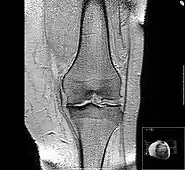

Diagnosis is made with reasonable certainty based on history and clinical examination.[51][52] X-rays may confirm the diagnosis. The typical changes seen on X-ray include: joint space narrowing, subchondral sclerosis (increased bone formation around the joint), subchondral cyst formation, and osteophytes.[53] Plain films may not correlate with the findings on physical examination or with the degree of pain.[54]